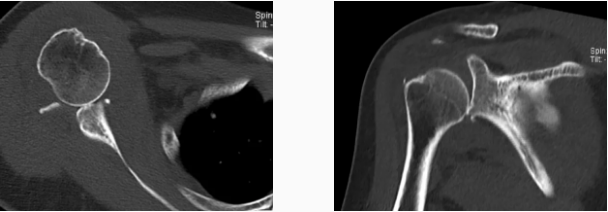

病例1

病史摘要:男性,44歲,跌傷致右肩關(guān)節(jié)疼痛數(shù)天,活動(dòng)不利。

CT圖示:右側(cè)肱骨后外上方局部骨皮質(zhì)塌陷,連續(xù)性中斷(箭頭);肩胛盂前下份邊緣變鈍,見高密度分離小骨片影(三角形)。